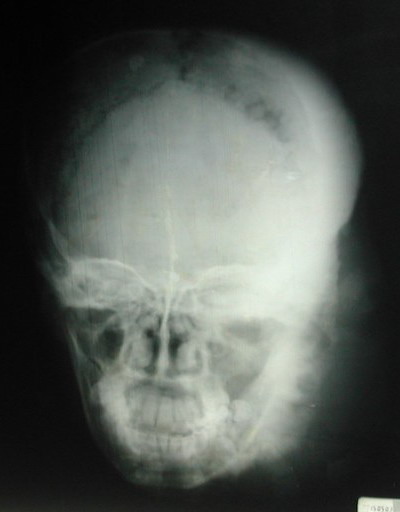

Skull Radiography showed a thinning of the left occipitoparietal vault with osteosclerosis and osteolysis areas and a widening of bone sutures (Figure 2). The osteosclerosis resulted from bone deposits that are perpendicular to the bone surface and extended from the second cervical vertebra to the sphenoid greater wing and the left mandible. The damage to the left eye was probably due to the inoculation of the causative agent in the eye after a trauma on the upper eyelid (Figure 3). However we did not carry out laboratory tests to confirm our observation.

Fig 2: X-ray showing osteosclerosis and osteolysis of the left side of the skull